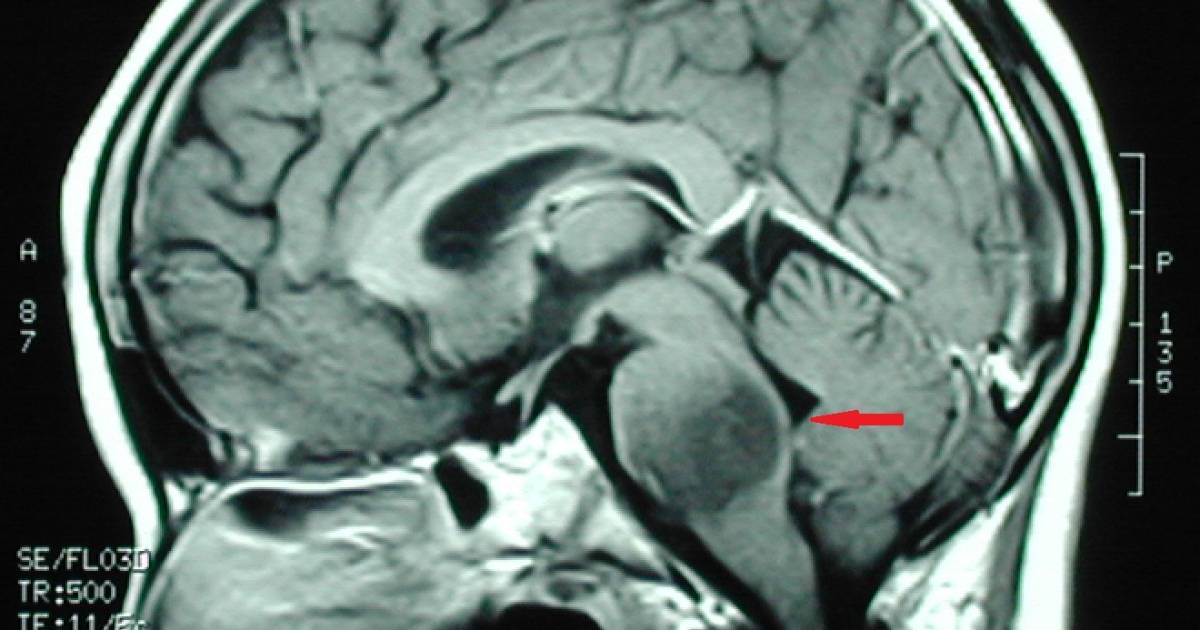

Los especialistas dieron a conocer que el tratamiento se basa en utilizar una mezcla de medicamentos que, en cierta secuencia, causan un efecto positivo en el tratamiento de los gliomas de tallo cerebral

Quienes padecen de esa enfermedad presentan un tumor que se llega a calificar como inoperable, sin embargo, los médicos de Monterrey, con una experiencia de 20 años trabajando de la mano, desarrollaron un procedimiento denominado quimioterapia intraarterial superselectiva, la cual ha dado una esperanza de vida a sus pacientes de todo el mundo.

En entrevista, los especialistas dieron a conocer que el tratamiento se basa en utilizar una mezcla de medicamentos que, en cierta secuencia, causan un efecto positivo en el tratamiento de los gliomas de tallo cerebral o incluso de otros tumores cerebrales.

Luego, explicaron, se hacen estudios de imagen para monitorear el avance que presentan los pacientes y en caso de no encontrarse actividad tumoral, se suspende el tratamiento y continúa en observación el paciente.